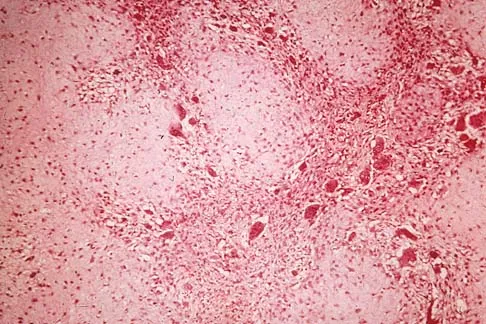

A 16-year-old boy has had thigh pain for the past several months. He denies any history of trauma. Examination reveals a large, deeply fixed, soft-tissue mass in the thigh. Laboratory results show an elevated erythrocyte sedimentation rate (ESR) and leukocytosis. A plain radiograph and MRI scan are shown in Figures 1a and 1b. Biopsy specimens are shown in Figures 1c and 1d. What is the most likely diagnosis?